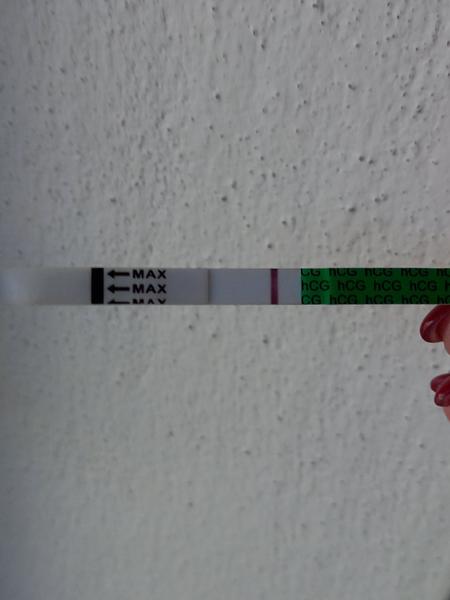

Duch na teste

ahojte babule, mam taku otazku...mate skusenost ze pocas 3 dni vam nesilnela druha ciarka na teste ale bola rovnaka???ako duch????

@zuzsat mne príde čiarka na teste @esmee3 jasná tiež.. a viditeľne sa postupne vyfarbuje. To už potom otázka testov a farby, a vylučovania hormónov, koncentrácii v mocu a tak. V porovnaní s tebou som zase mala veľmi nízke hcg.. a strašne pomaly to stúpalo, odmietla som hospitalizáciu lebo si mysleli všetci že to je mimoM tehotenstvo, teraz som v 23tt. Každý je v niečom iný..

@zuzsat baby uvidíme na sono ideme týždeň tak uvidíme. Len určite aj trvalo tomu vajíčku sa vôbec spojiť čiže reálne to mohlo byt až v nedeľu večer niekedy, a ja som testovala minulý pondelok a tam nebolo nič ani duch na 9dpo, prvý duch bol až v piatok, čo bolo 13dpo a to vtedy ukázal aj digi test poobede. Tak ja stále nestrácam nadej do utorka 😊je vidieť že tie testy sú raz tak silnejšie po tých 2dnoch, a možno už aj ten digi by ukázal 2-3t, v piatok bolo 1-2 neviem nemám doma iný test okrem týchto z dm

@zuzsat ja vidím aj bez upravenia 🤞🤞🤞 moc moc moc držím palce ❤️koľko si dpo?

@zuzanaa2010 si zlata ale nechce sa mi verit .. kym nie je poriadne vidiet stale budem na pochybach

@esmee3 je to individuálne, mne pri prvom silnela oveľa pomalšie ako pri druhom 😎 nestresuj sa zbytočne testami. Niekto už á ducha 9 DPO a niekto až 13 DPO 😉